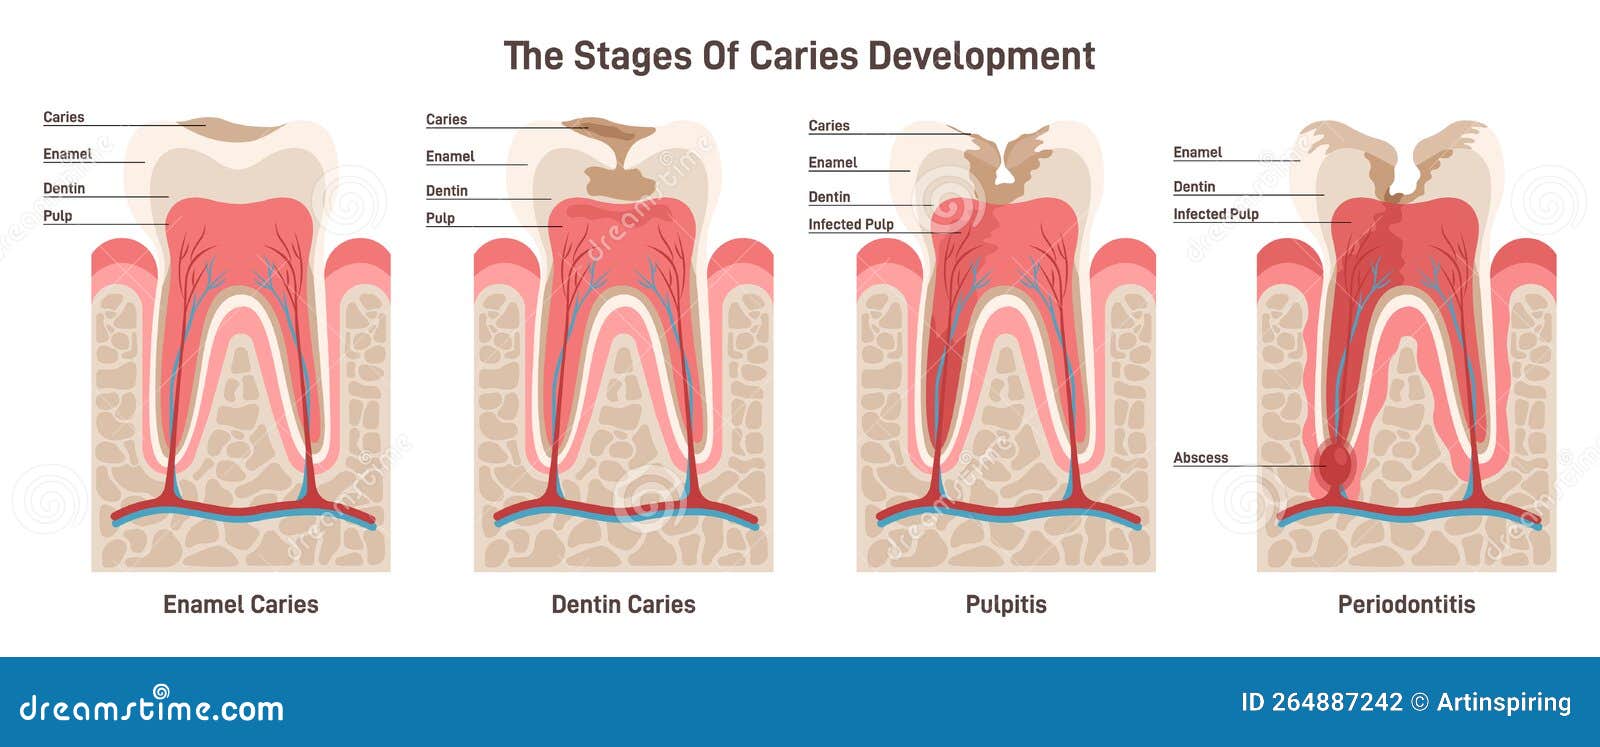

caries tooth pulpitis periodontitis

Caries Development. Dental Disease Stages: Enamel And Dentin Caries

www.dreamstime.com

www.dreamstime.com

Tooth dental decay abscess stages caries dentagama phoenix pain pulp infection teeth bone like spread look mouth periodontal severe enamel. Symptoms and treatments of dental caries. Stages of dental decay and periodontal disease